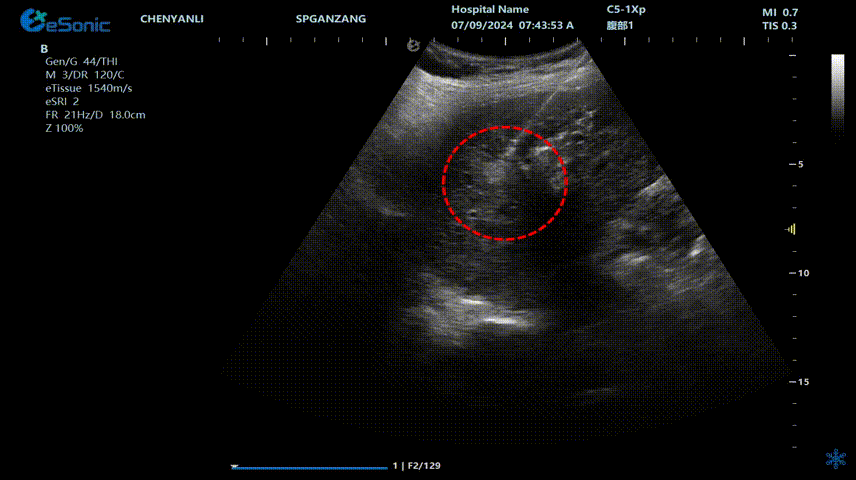

640 (2).gif

肝癌射频消融动态视频

红圈为病灶位置

肝癌射频消融:全麻下彩超探头引导射频针分别植入肝右叶两个稍高回声结节,固定消融,至结节全部为强回声覆盖,覆盖良好,缓缓灼烧针道后退针。